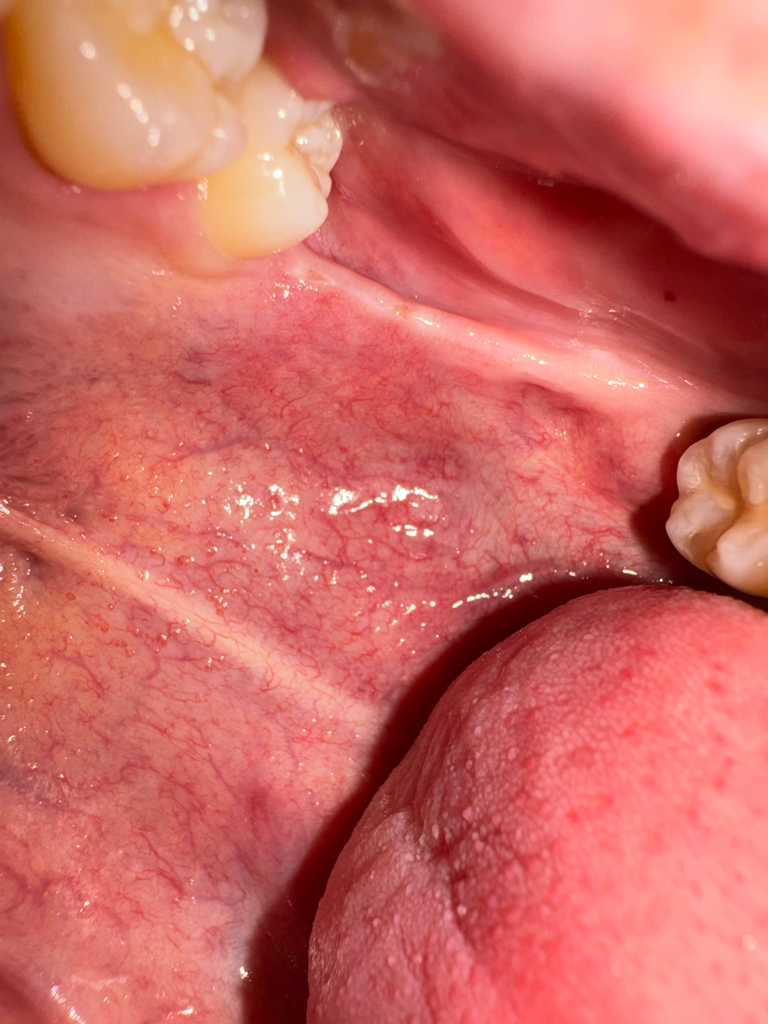

왼쪽 위아래 사랑니가 나야할 자리에 위아래로 연결된 끈 같은게 있는데 한 두달전부터 입벌릴때마다 땡기고 아픕니다. 오른쪽 아래어금니 크라운을 씌울 때 입을 계속 벌리고있었는데 그 때부터 의식하게돼서그런지 자꾸 신경쓰입니다. 사랑니가 나는 자리에도 약간 꺼끌꺼끌하게 상처같은게 나있는 것 같아요(혀로 만지면 느껴집니다.) 입을 최대한 크게 벌리면 저 끈같은게 끊어질 듯 아프고 사진도 자세히 보시면 말씀드린 끈같은것에 노란색 고른같은게 있어보입니다. 구강암같은 것일까요...? 치과에서는 별 말씀 없으셨었습니다.

1. 해당 구조는 pterygomandibular raphe라고 하며 정상 구조물입니다.

2. 오른쪽 위,아래로는 사랑니가 있고 왼쪽의 경우 아래는 사랑니가 있습니다.

3. 노란색은 구강 내 지방조직 내지는 염증으로 추측됩니다.

저부위에 상처가 생겨서 그러는거 같으니 당분간은 입을 크게 벌리는건 조심하시고 그쪽부위에 자극이 가지 않도록 해주시는게 좋을것같습니다.